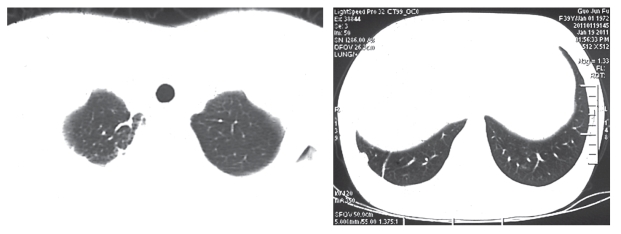

学习阅读影像资料,需要下点功夫,但有些部位的影像资料也不是很难懂。我们只需学习了解本病中最重要的部位,也是最常做检查部位的影像阅片就可以了。阅片先要大体上知道成像原理。以肺部CT为例,它是对人体肺部进行断层扫描的结果,就像把土豆切成片状一样,相当于把整个肺部一层层地横切开来让我们看。所以,我们看到的肺部CT片子,最上边是肺尖和气管,然后进一步看到支气管、肺门和肺的大部分组织,到了最后,就只剩下两肺下端,就像月牙形了(见图2)。

图2 肺尖和两肺下端CT影像图